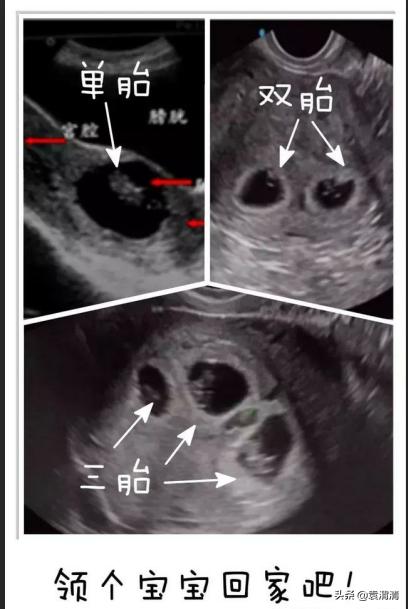

2、看看单胎、双胎还是多胎

妊娠早期进行彩超检查可以明确胚胎的数目,看看此次妊娠是单胎还是多胞胎。同时,通过观察胎芽的长度和是否有胎心搏动,可以评价胚胎的状态。